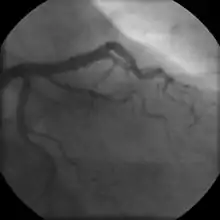

- Coronary angiography

In "stable" angina, chest pain with typical features occurring at predictable levels of exertion, various forms of cardiac stress tests may be used to induce both symptoms and detect changes by way of electrocardiography (using an ECG), echocardiography (using ultrasound of the heart) or scintigraphy (using uptake of radionuclide by the heart muscle). If part of the heart seems to receive an insufficient blood supply, coronary angiography may be used to identify stenosis of the coronary arteries and suitability for angioplasty or bypass surgery.[64]